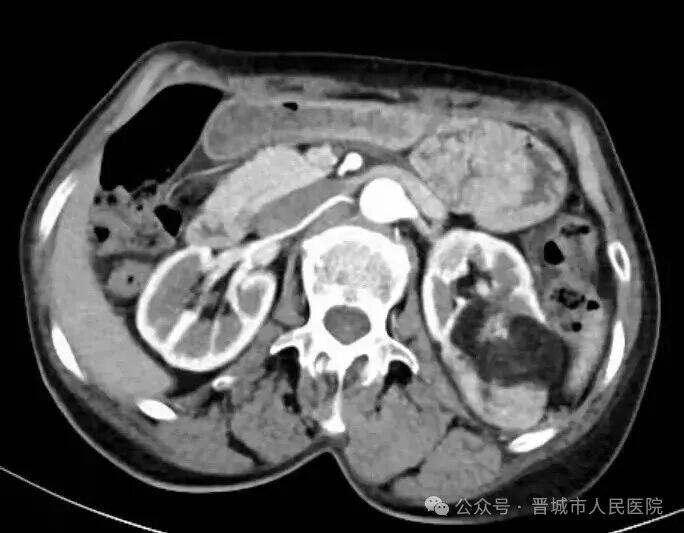

据了解,患者因体检发现左肾占位20余天入院,外院检查提示左肾肿物大小约45*55*98mm,接近十公分的肿瘤体积给治疗带来了极大挑战。更为棘手的是,患者年事已高,体质薄弱且营养状况欠佳,腹壁肌肉薄弱导致手术戳卡固定困难,传统腹腔镜手术操作空间受限、难度极高,而患者及家属保肾意愿十分强烈。

手术过程中,机器人系统的多自由度机械臂展现出独特优势,可灵活模拟人手动作,突破传统腹腔镜的操作角度限制,在狭小的术野内实现精细分离与操作。配合高清3D视野系统,术者能清晰辨识肾脏血管与肿瘤边界,精准把控手术节奏,有效规避血管损伤风险,为肿瘤完整切除和肾脏功能保留奠定了基础。

术前,团队还组织多学科病例讨论,针对肿瘤位置深、血供丰富的特点,量身制定个性化手术方案,充分预判术中可能出现的风险并制定应对策略,将微创技术与精准医疗理念深度融合。